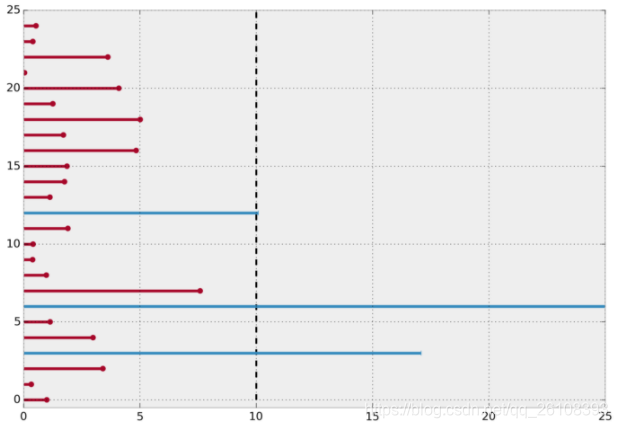

以样本的出生和死亡为例,我们观测一组样本的生存时间。然而我们观测和追踪他们是需要时间和金钱的成本的,不可能因为样本一直存活着,我们就一直将某个实验做下去。通常,专家只会对一组样本观测一段时间,例如,两年或者两个月。有些样本在观测期间触发了目标事件(death),而有些样本直到实验观测结束也没有触发目标事件,我们称没有触发目标事件的样本有右侧截断。

考虑这样一个例子:我们观测的目标人群实际上是来自两个不同的组(可以简单理解为患了不同的病),他们的平均存活时间是不一样的,假定A组的平均存活时间只有两个月,而B组的平均存活时间有十二个月。值得注意的是我们现在是把他们全部放在一起观测的,我们并不知道谁是A组谁是B组,而我们的目的是想知道这些人平均会活多久。 假定我们的实验进行了十个月就结束了。

如果我们只是简单地删除那些发生右侧截断的样本,然后对所有人的生存时间求平均,我们将会严重低估这个群体的生存时间。

如果我们不删除发生右侧截断的样本而直接求平均值,仍然会低估这个群体的平均生存时间,要注意的是,我们只能观测到10时刻之前的事情,10时刻之后的我们并不能看到。

上述例子是为了阐述方便所以让所有的样本的出生从0时刻开始,而实际上这是不必要的,生存分析并不要求所有样本在同一时刻出生,它只关注每个样本从出生到death触发或到实验结束之间的间隔时间,每个样本随时可以出生。